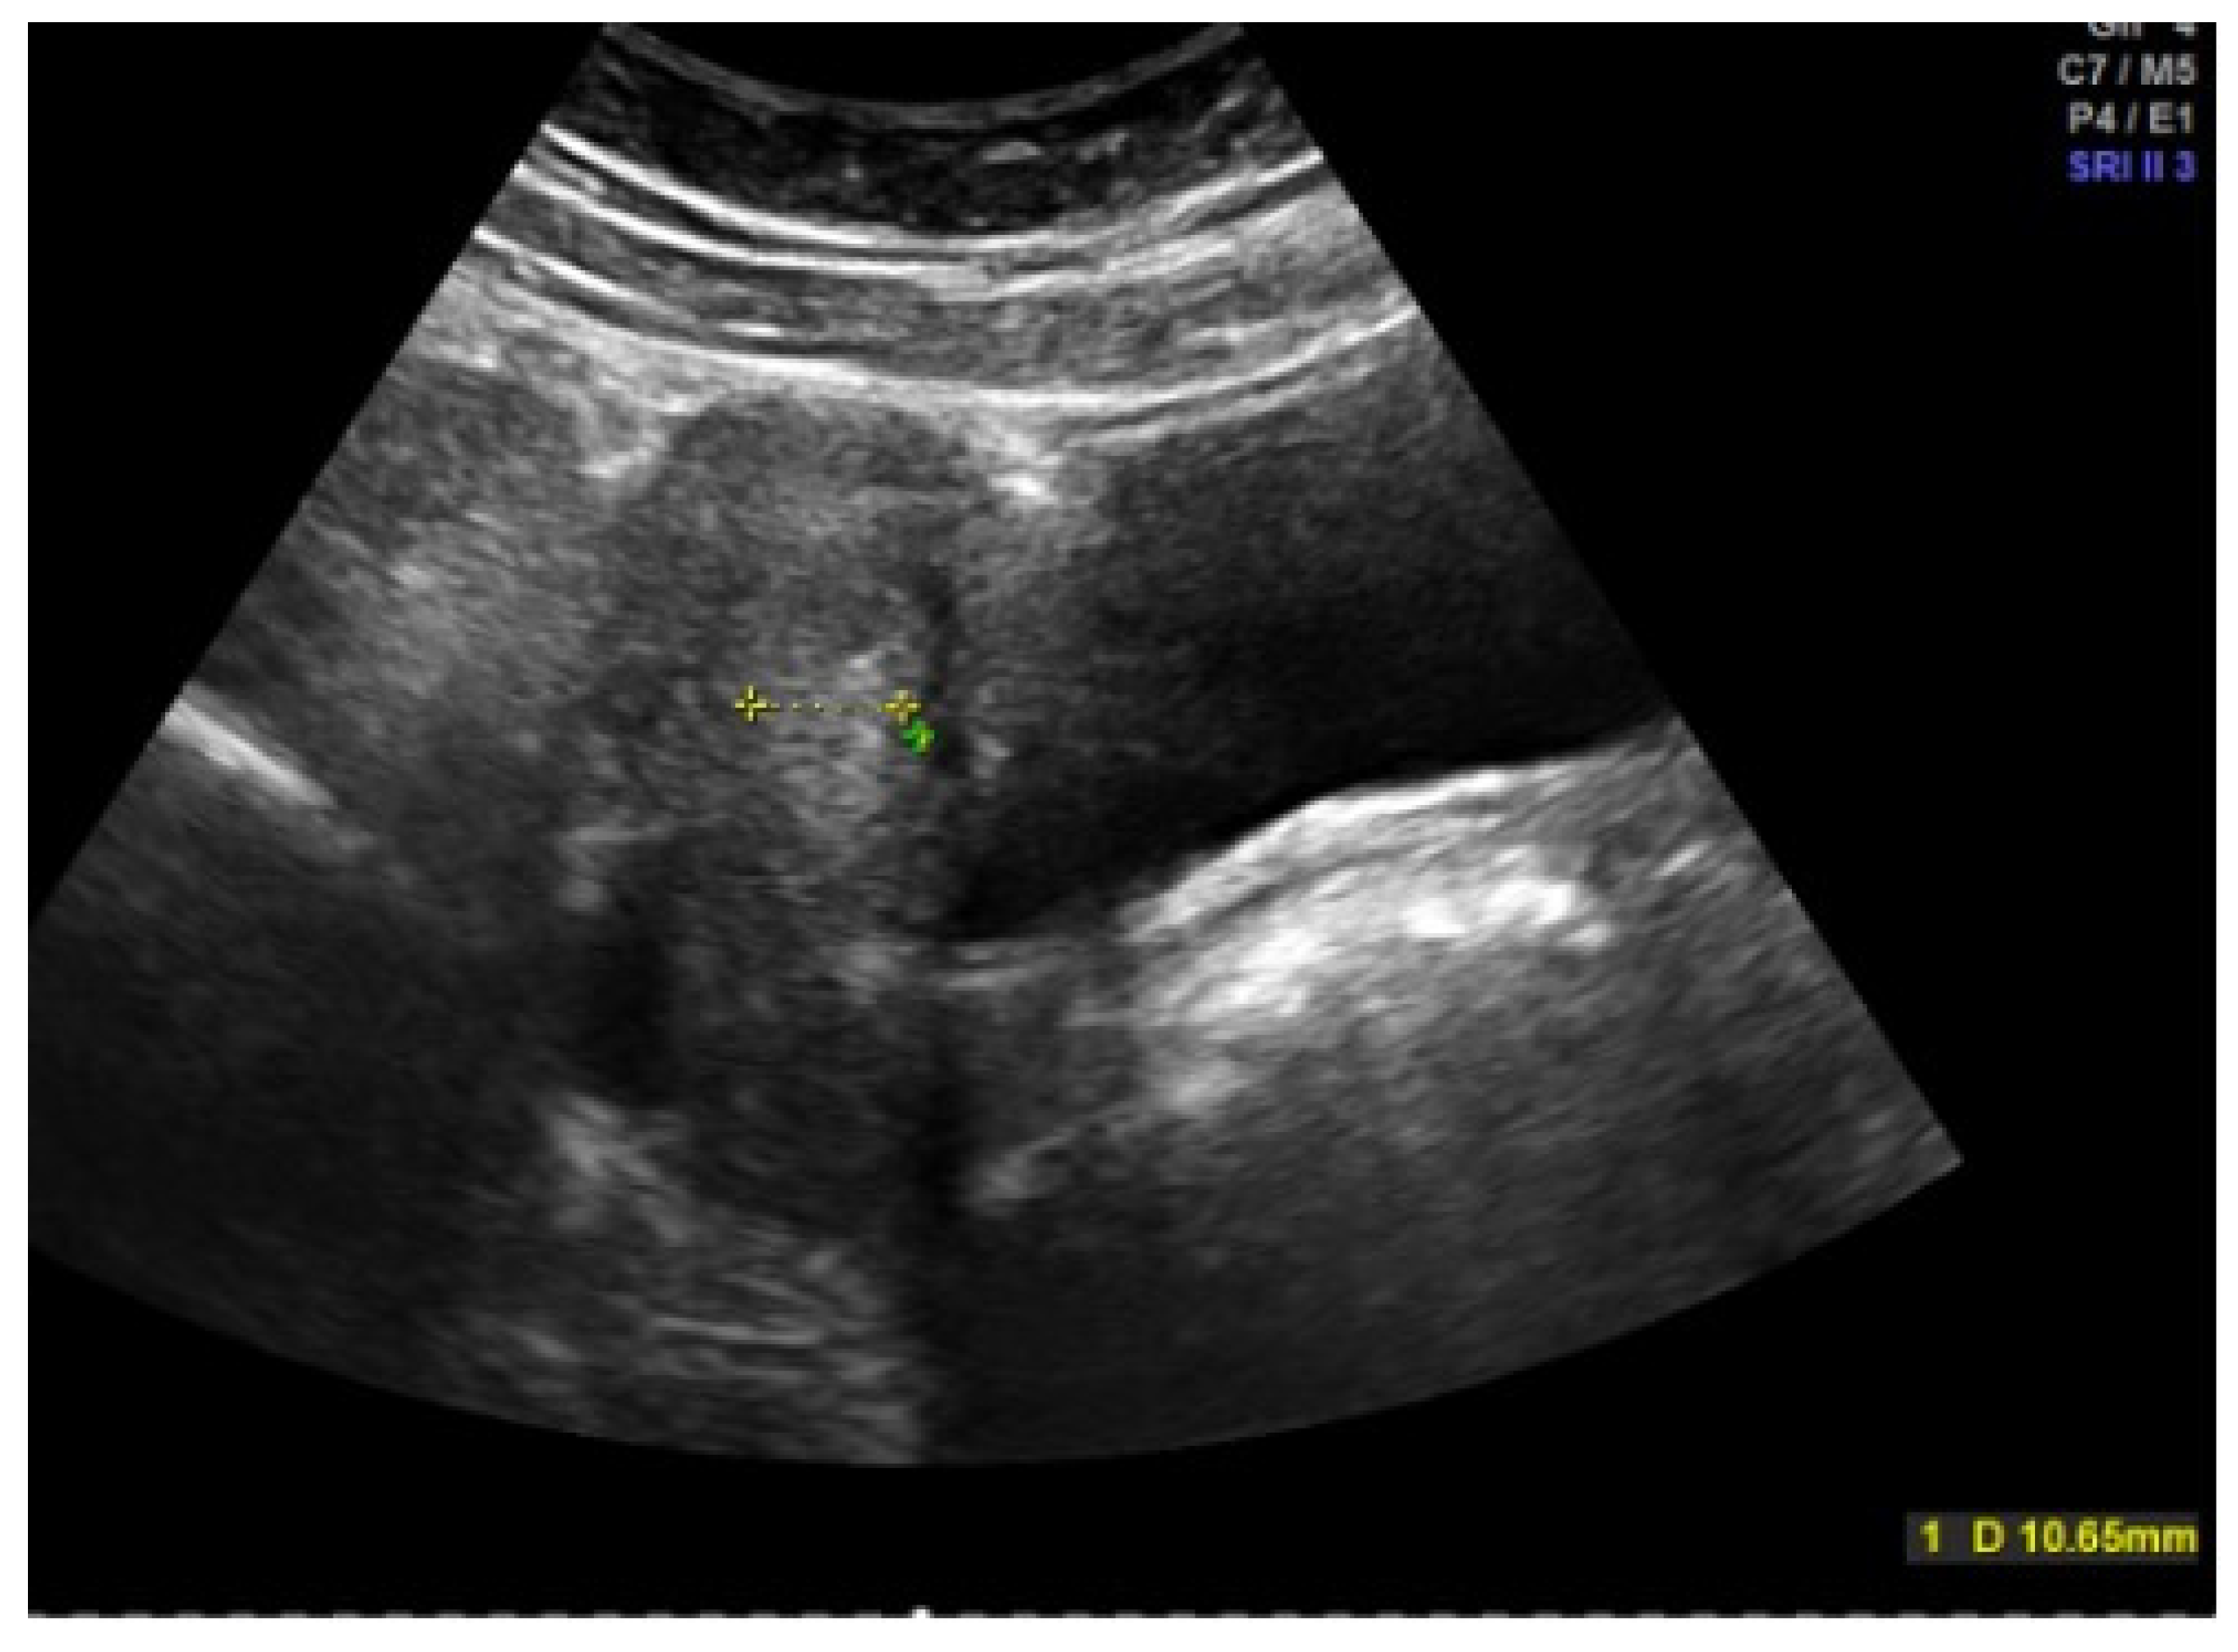

- Martire, F.G.; Lazzeri, L.; Conway, F.; Siciliano, T.; Pietropolli, A.; Piccione, E.; Solima, E.; Centini, G.; Zupi, E.; Exacoustos, C. Adolescence and Endometriosis: Symptoms, Ultrasound Signs and Early Diagnosis. Fertil. Steril. 2020, 114, 1049–1057. [Google Scholar] [CrossRef] [PubMed]